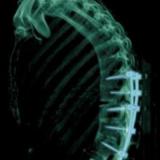

Кубанские врачи провели уникальную операцию на кривом позвоночнике

46-летняя пациентка пришла к врачам на консультацию. Тогда ее позвоночник был настолько деформирован, что когда она стояла, верхняя часть ее туловища была параллельна земле. Эта хроническая воспалительная патология называется болезнью Бехтерева....